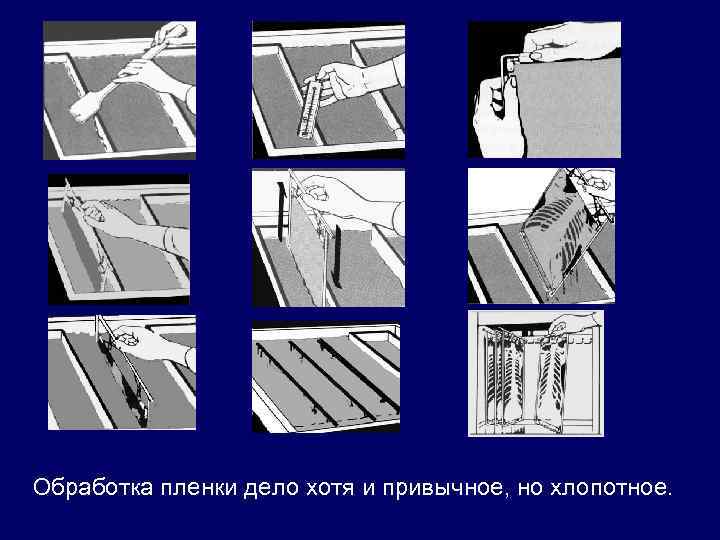

Обработка пленки дело хотя и привычное, но хлопотное.

Проявочные автоматы решили задачу быстрой обработки пленки. Вмешательство в процесс проявления исключена и многие их за это не любят. Но потом привыкают и жизни без процессоров уже не видят.